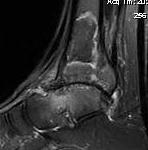

MRI